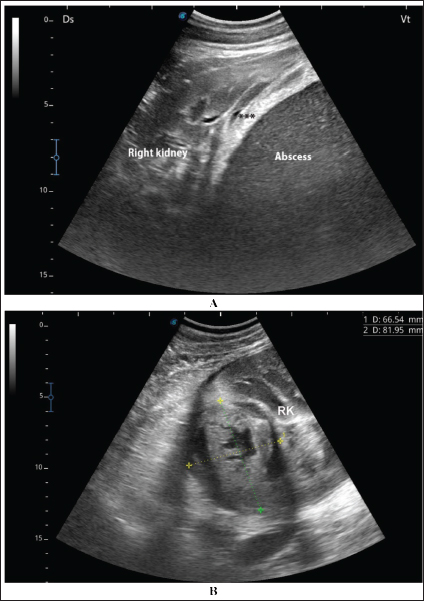

Fig. 5. Ultrasonographic findings in camel numbers 2 (A) and 4 (B) with right kidney abscesses. The abscess in image A appeared markedly large and compresses the renal parenchyma with echogenic contents and a thickened capsule (stars). The lesion in image B is compressing the parenchyma of the right kidney (RK) and measuring 6.7 × 8.2 cm with echogenic contents and a thick capsule.

A detailed description of the renal abscesses is presented in Figures 410. Figure 4 shows sonographic findings in camel number 1 with abscessation of the right and left kidneys. A large abscess measuring 12.5 × 11.6 cm with hypoechoic contents and a thick capsule was detected. A second abscess in the same camel was imaged compressing the parenchyma of the right kidney and measuring 7.2 × 7.9 cm with echogenic contents and a thick capsule. Figure 5 shows ultrasonographic results in camel numbers 2 and 4 with right kidney abscesses. The lesions in camel number 2 appeared markedly large, compressing the renal parenchyma, with echogenic contents and a thickened capsule. The lesion in camel number 4 appeared to compress the renal parenchyma of the right kidney, measuring 6.7 × 8.2 cm with echogenic contents and a thick capsule. In addition, Figure 6. clarifies sonographic findings in camel number 6, where the abscess appeared within the right kidney. The contents were heterogeneous, but the capsule could not be imaged. The urinary bladder in the same animal was imaged with echogenic deposits that appeared highly echogenic compared with the echogenic urine.